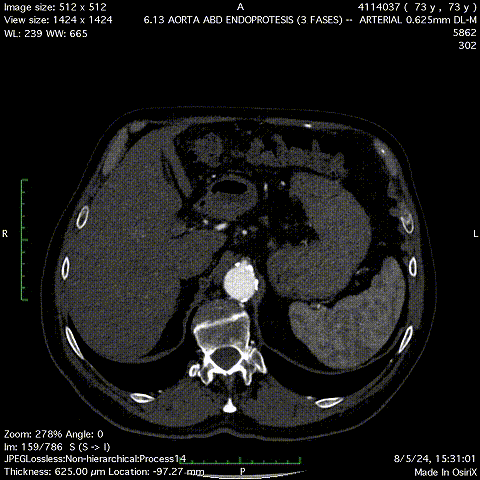

患者男性,73岁,腹主动脉瘤,高血压、血脂异常、慢性肾病。右侧股动脉中度钙化,直径5.4mm,入路面临挑战。选用Minos覆膜支架进行治疗,手术过程顺利,术后1个月的CT扫描显示无内漏且肢体通畅。该案例体现了Minos覆膜支架的Low Profile的低外径输送系统能够在狭窄和迂曲的动脉中顺利操作,为因血管条件不佳而不适合传统EVAR的患者提供了新的治疗选择。